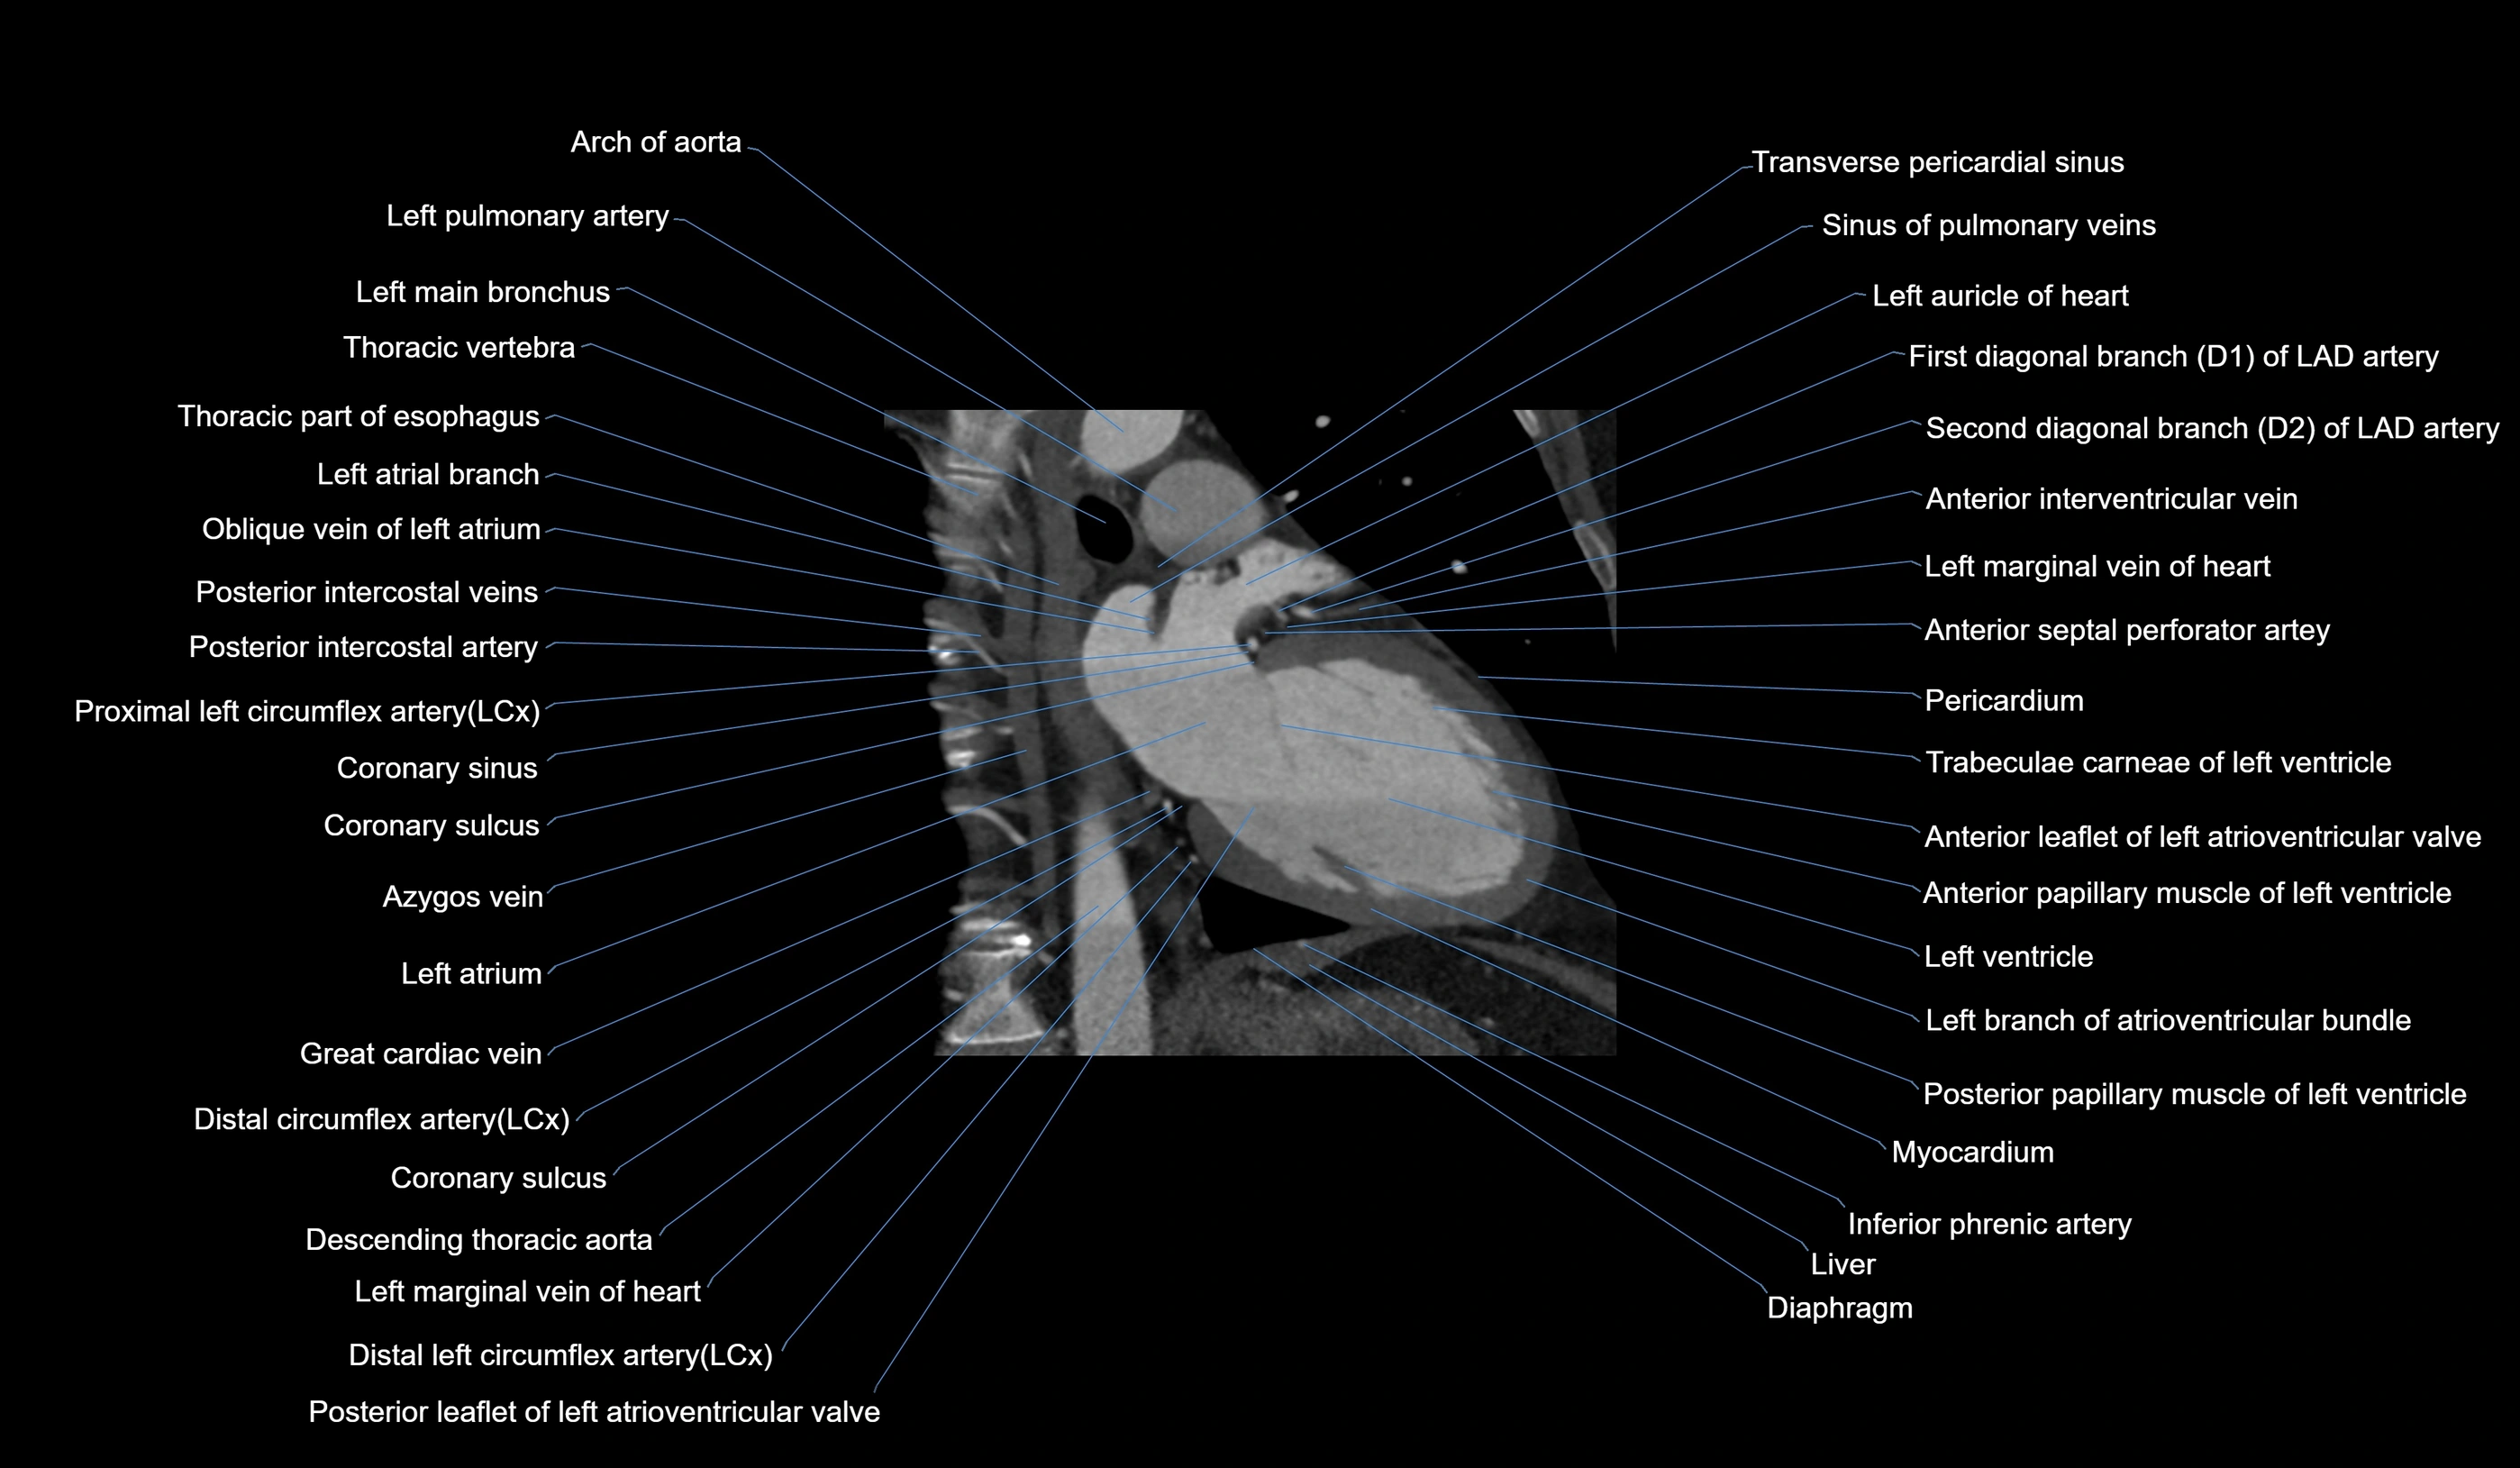

CT images